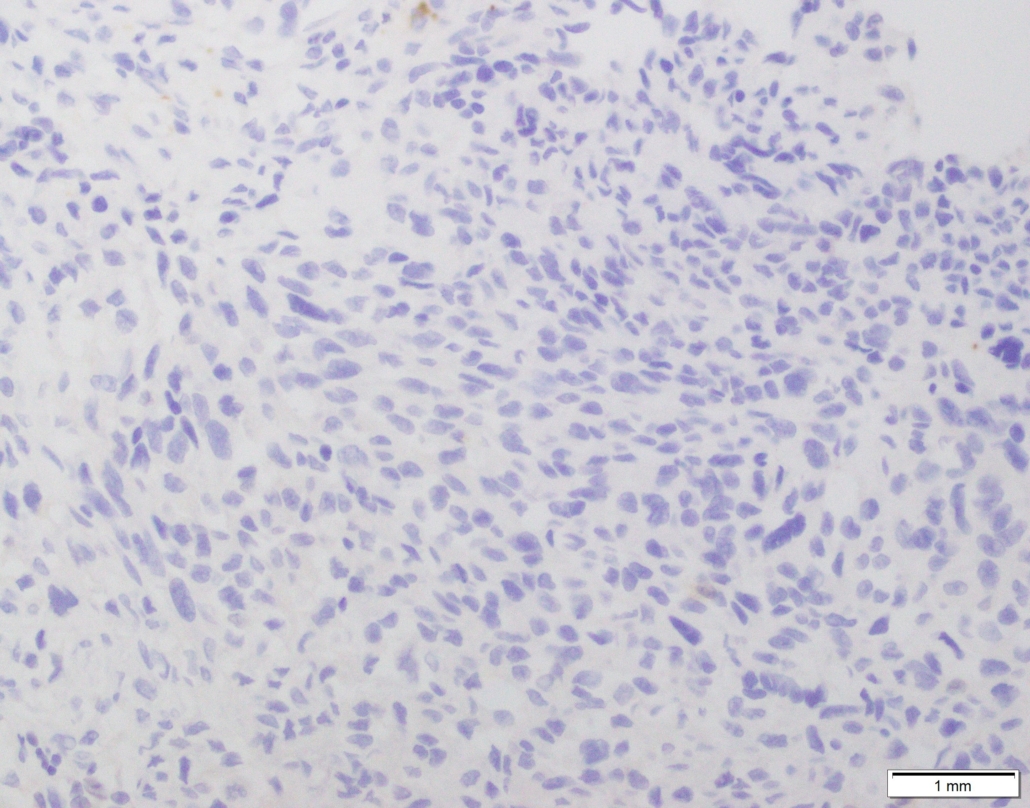

Case 03

Case presented by Dr Shaarif Bashir, FCPS (PAK), Shaukat Khanum Memorial Cancer Hospital and Reserach Centre, Pakistan